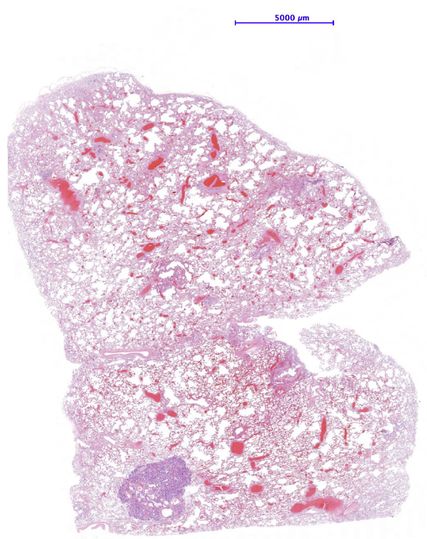

Abb. 1:Im Übersichtsbild kommt der kleine Knoten deutlich hervor. Maßstab 5000µm

Der ziliäre papilläre mukonoduläre Tumor der Lunge ist eine neue Entität, der eine charakteristische Morphologie aufweist (Abb. 1–4). Aufgrund der bisherigen Berichte kann von einer geringen Malignität ausgegangen werden. Die molekularen Signaturen lassen aber die Möglichkeit einer Rezidivierung und eventuell sogar einer Metastasierung offen.Dementsprechend kann eine Prognose nicht mit Sicherheit abgegeben werden. Eine engmaschige Kontrolle in den ersten fünf Jahre nach Diagnose ist zu empfehlen.